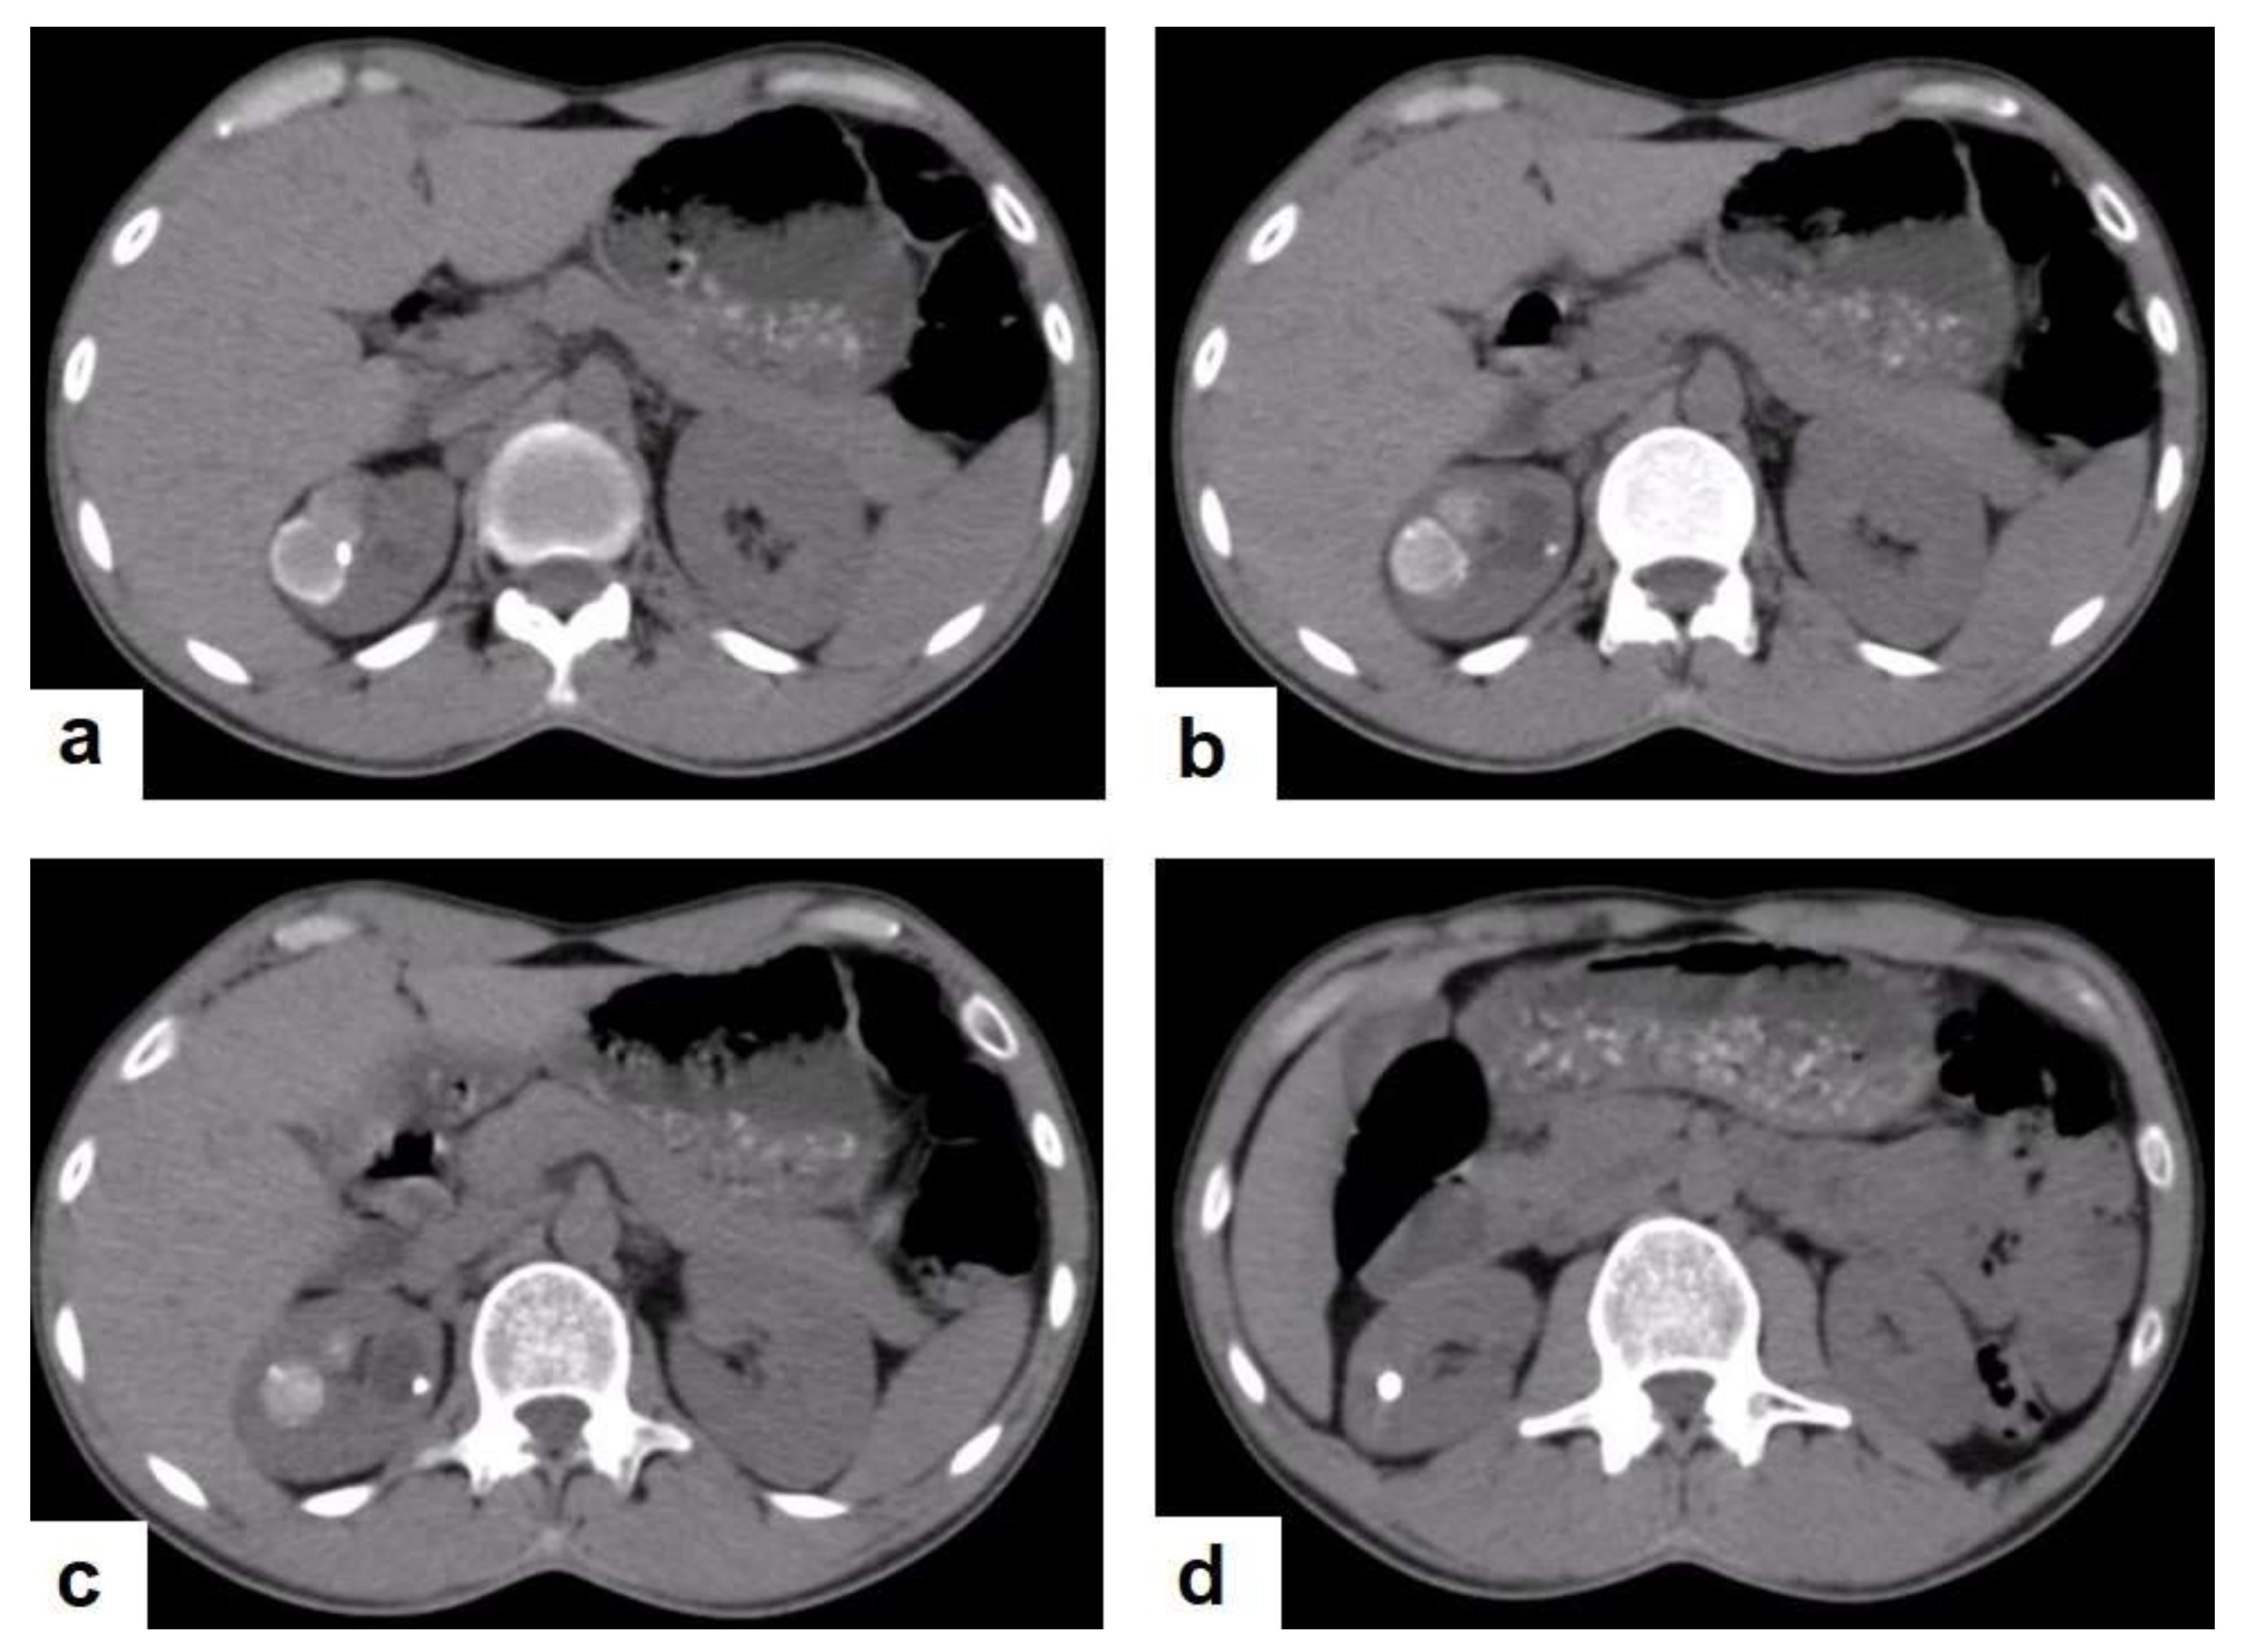

Figure 22. Fibrotic peritonitis in a 20-year-old man with fatigue, abdominal distension, and loss of appetite. Selected axial images of abdominal CT show remarkable omental thickening, forming cake-like masses (arrows) with faint enhancement and mild smooth thickening of peritoneal reflections associated with mild-to-moderate dense ascites and several low-attenuation mesenteric lymph nodes that are challenging to be distinguished from small bowel loops.

• Fibrotic peritonitis (Figure 22) is characterized by remarkable omental and mesenteric thickening forming cake-like masses with bowel loops enlargement and matting that can be seen by CT or ultrasound. [46,47].